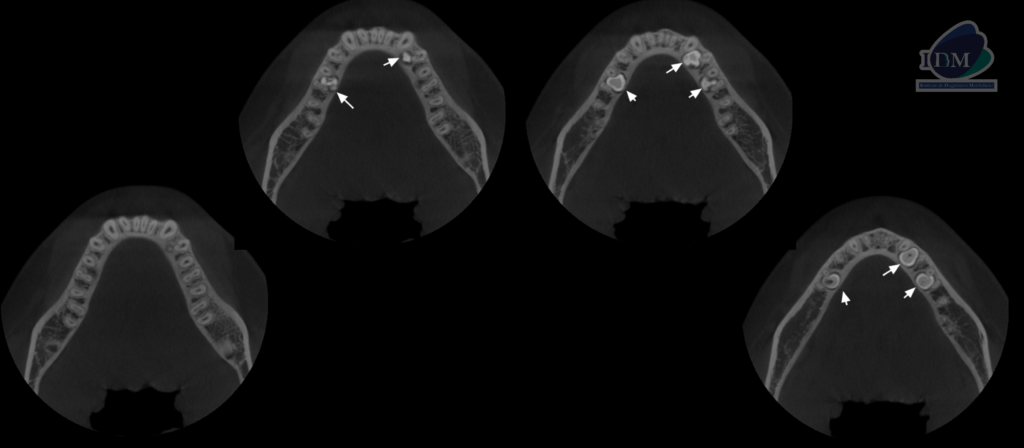

CORTES AXIALES